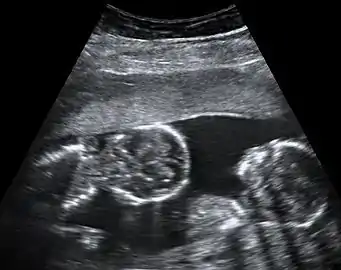

Abdominal ultrasonography of monoamniotic twins at a gestational age of 15 weeks. There is no sign of any membrane between the fetuses. A coronal plane is shown of the twin at left, and a sagittal plane of parts of the upper thorax and head is shown of the twin at right.

Monochorionic twins generally have two amniotic sacs (called Monochorionic-Diamniotic "MoDi"), but sometimes, in the case of monoamniotic twins (Monochorionic-Monoamniotic "MoMo"), they also share the same amniotic sac. Monoamniotic twins occur when the split takes place after the ninth day after fertilization.[2] Monoamniotic twins are always monozygotic (identical twins).[3] Monochorionic-Diamniotic twins are almost always monozygotic, with a few exceptions where the blastocysts have fused.[2]